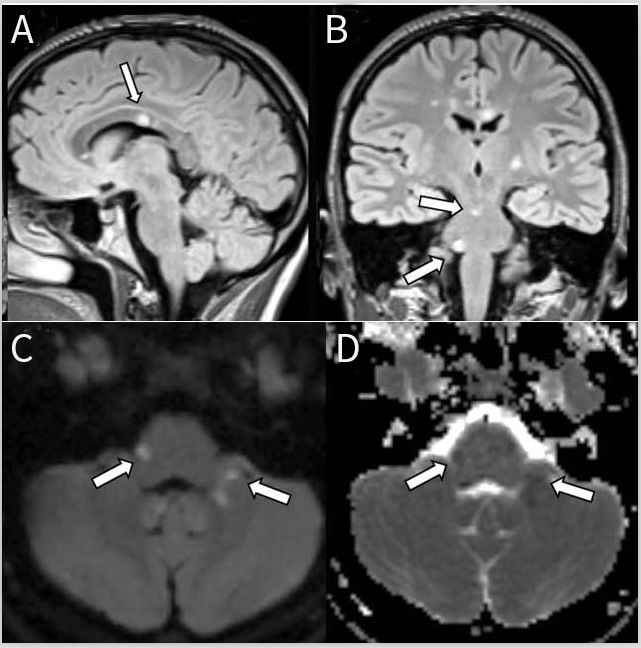

Susac综合征(SS)是一种小动脉内膜疾病,临床表现包括脑病、视网膜分支动脉闭塞和低频感觉神经性听力损失。SS被认为具有免疫介导的病因,涉及体液和细胞致病途径。

耳科受累可通过听诊确认。包括荧光素血管造影在内的视网膜检查可发现视网膜分支动脉闭塞、Gass斑和荧光素泄漏。通常通过头颅MRI证实神经系统受累,其中高度特征性的是胼胝体病灶呈冰锥样、轮辐样或雪球样改变。其他典型的MRI表现为点状脑室周围白质和深部灰质T2 / FLAIR高信号改变。急性病变典型表现在MRI上为弥散受限,内囊多发“珍珠串”病灶。薄的软脑膜增强较常见,尤其是小脑上方,急性期实质病灶可以增强。而在NS,软脑膜增强常为结节状,在AQP4-IgG阳性NMOSD中,软脑膜增强常为线性增强且在急性复发期间会出现实质或实质周围增强。SS的磁共振血管造影常为正常,而SWI通常不会显示出铁血黄素的沉积。据报道,SS患者中有30%的患者有脑干受累。病变的点状性质可能被误认为CLIPPERS的脑干病变,但SS病灶增强较少见,急性期可见弥散受限,胼胝体和大脑其他部位的特征性MRI表现通常可以将SS与其他疾病鉴别开(图6)。CSF蛋白显着升高较常见(通常>1.5g / L),很少有细胞增多,无CSF寡克隆带。

图6 Susac综合征患者的MRI影像。矢状位FLAIR序列(A)显示胼胝体存在典型的“雪球”病变。(B)冠状位FLAIR图像还可见脑桥上另外有一处点状和更大的病灶(箭头)。弥散加权成像(C)和表观弥散系数序列(D)显示活动性病灶存在弥散受限(箭头)。

朗格汉斯细胞组织细胞增生症(LCH)和非朗格汉斯细胞组织细胞增生症[包括Erdheim Chester病(ECD)]被列为恶性疾病,通常在脑干中出现实质性炎症性病变。LCH一般儿童期发病,而ECD见于成年期。全身表现包括骨痛(LCH累及颅骨/ ECD累及长骨)、皮肤和内脏受累,以及中枢神经系统。

20%至50%的LCH患者会累及中枢神经系统。尿崩症很常见,垂体茎、脉络丛、脑膜、脑干或眼眶可能会出现明显强化性占位病变。小脑、基底神经节(尤其是苍白球)和脑桥的神经退行性病变表现为进展性对称性T2高信号病变。

在27%的LCH患者的MRI中可见脑干受累,通常与齿状核和白质受累同时发生,冠状位可见蝴蝶翅征。在脑桥锥体束或被盖白质中可见斑片状T2高信号病灶,可出现斑驳状外观,蔓延至小脑脚(图7)。LCH和CLIPPERS的MRI表现可能非常相似,但LCH往往具有较大的结节,T2高信号病灶范围比T1强化病灶更大;还可见增大的血管周围间隙、实质强化和弥漫性白质脑病。

图7 朗格汉斯细胞组织细胞增生症患者MRI影像。轴向FLAIR(A)显示脑桥和邻近的小脑半球弥漫性和不均匀性高信号,呈斑驳的外观。轴位(B)和冠状位(C)T1增强图像可见脑桥病灶呈斑点状强化。